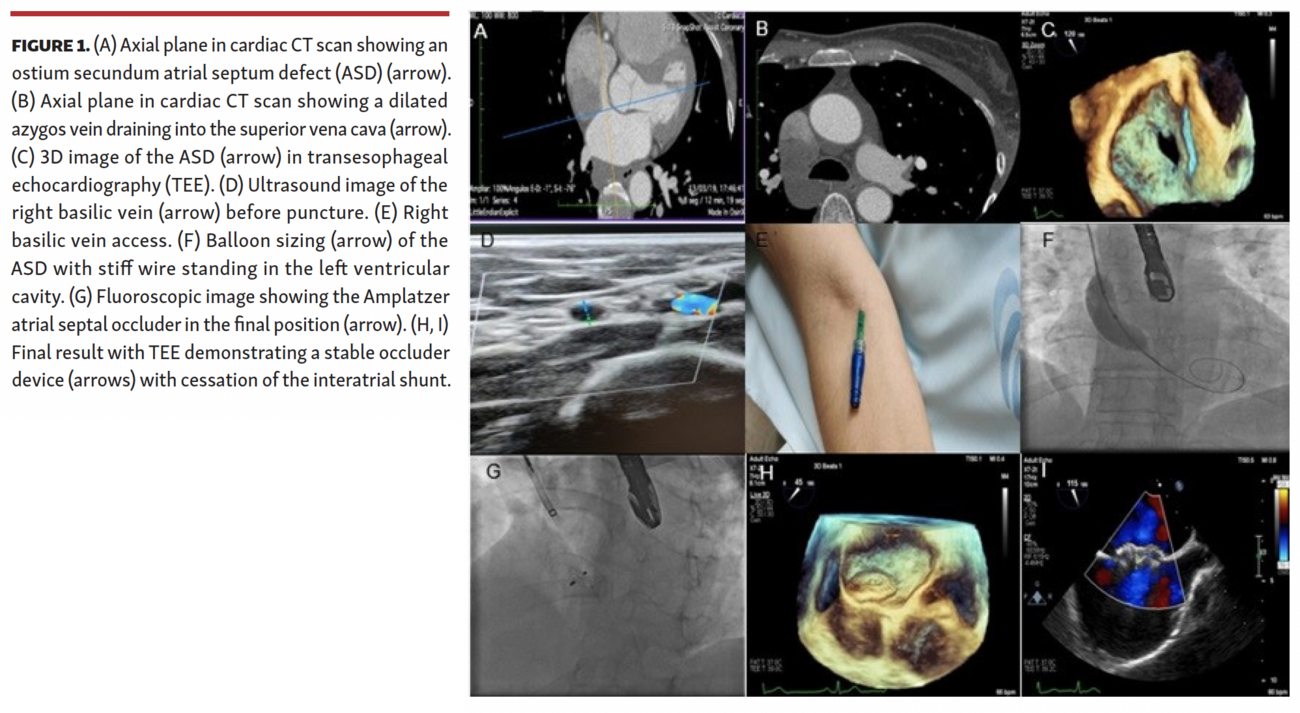

Atrial septal defect (ASD) closure is indicated in the presence of a significant left-to-right shunt. The preferable treatment is transcatheter closure, usually performed by transfemoral route. However, in the case of an interrupted inferior vena cava (IVC), the standard percutaneous approach can be troublesome. The authors report a case of a 55-year-old woman with an ostium secundum ASD with a significant left-to-right shunt at rest (Qp/Qs, 1.6). Her diagnosis and treatment are shown in Figure 1. The cardiac computed tomography scan showed an interrupted IVC above the renal veins. The patient was referred for percutaneous defect closure, through an ultrasound-guided right basilic vein access. The procedure was performed using transesophageal echocardiography guidance. A 7 Fr sizing balloon and Amplatzer TorqVue delivery system (Abbott) were introduced through the basilic vein. A 15 mm Amplatzer septal occluder device was used with a good final result.

To our knowledge, this is the first case in the literature featuring the transbasilic peripheral vein approach for ASD closure.